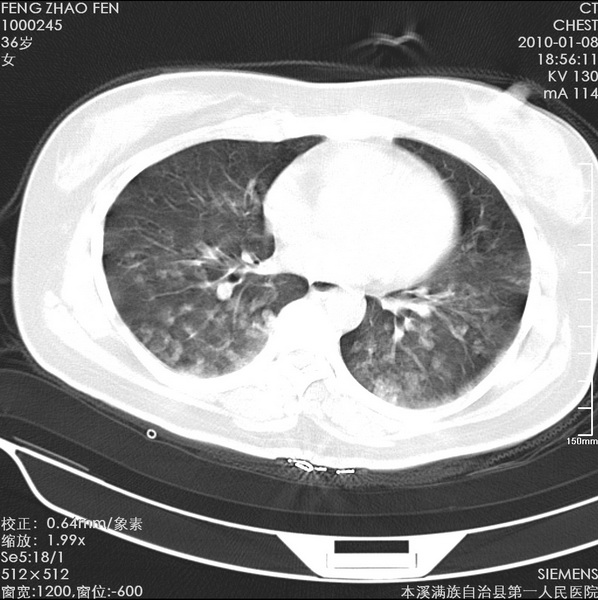

标题: CT24051:双肺多发斑片状阴影 [打印本页]

标题: CT24051:双肺多发斑片状阴影

女、36、咳嗽、咯血,余不详。